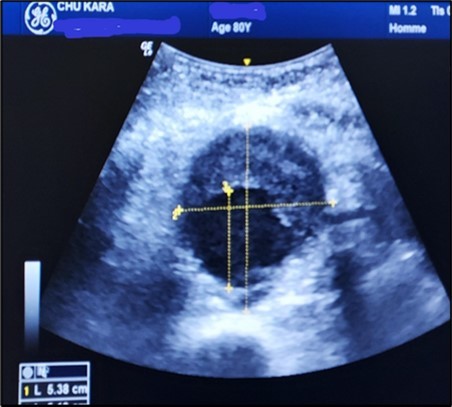

The aneurysms had extensions to other arteries in 21 patients (65.63%) distributed as follows: superior mesenteric artery (11.76%) (Figure 3) and (Figure 4), celiac trunk (14.23%), iliac arteries (57.14%) femoral arteries (19.05%). (Figure 5) and (Figure 6)

Figure 5.Subrenal AAA of 5.38 cm partially thrombosed in half in an 80-year-old subject (CHU-Kara).